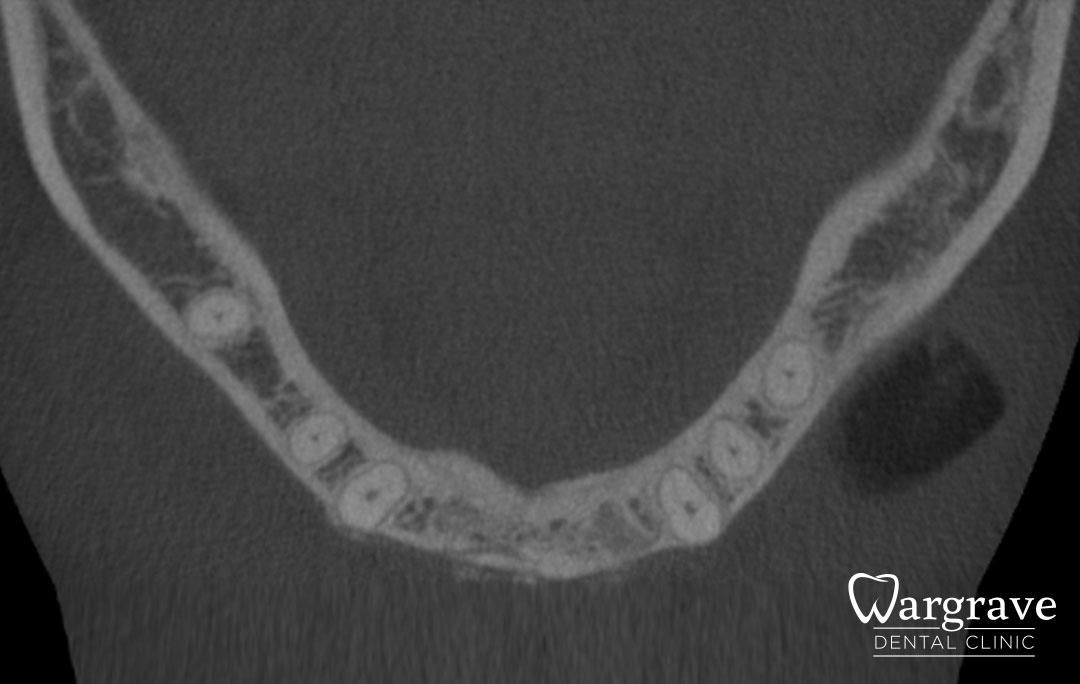

After

Before

This patient presented with a very narrow anterior mandible and insufficient bony width for dental implants. An extensive grafting procedure was carried out. Several months later the site was restored with a four unit fixed Implant Bridge on two implants